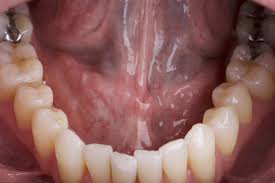

What Does Mouth Cancer Look Like On The Tongue / Tongue Cancer Symptoms Pictures Prognosis : Oral cancer can affect the mouth including the gums, lips, tongue, mouth's roof, and floor and the inner cheeks.. The main risk factors are smoking, drinking a lot of alcohol and infection with the hpv virus. It may be numb or firm to feel and doesn't fade away over time. Floor of the mouth cancer most often begins in the thin, flat cells that line the inside of your mouth (squamous cells). Canker sores can be found anywhere in the mouth from the cheek, inner lip, on and under the tongue, and even in the throat. The middle of the canker sore may appear white, gray, or yellow, and the edges are red.

Tongue Cancer Symptoms Pictures Prognosis from post.healthline.com What does tongue cancer look like? It may be numb or firm to feel and doesn't fade away over time. Those with tongue cancer will usually have an unusual spot or sore that is visible on his or her tongue. Mouth cancer usually presents with distinctive symptoms and features, such as red or white patches in the mouth, changes in oral tissue, or difficulty chewing or swallowing. Visible mass in the mouth. A canker sore looks like an ulcer, usually with a depression in the center. A patch on your tongue, gums, tonsils, or the lining of your mouth can signal trouble. They may look like a patch or a lump or look like an ulcer.

Those with tongue cancer will usually have an unusual spot or sore that is visible on his or her tongue. What does tongue cancer look like? A canker sore looks like an ulcer, usually with a depression in the center. Abnormal cell growth usually appears as flat patches. Women and people of 45 years of age and above are more vulnerable to. The most common precancerous conditions of the mouth are leukoplakia and erythroplakia. The lump may be white in color and look like an ulcer. The middle of the canker sore may appear white, gray, or yellow, and the edges are red. Symptoms can include a patch, spot or lump on your tongue that doesn't go away. Canker sores also look different than patchy mouth cancer. Signs and symptoms may include: The characteristics of these lumps include: Risk factors for tongue cancer include being male, over 40, and a smoker.

These photos give you an idea of what possible mouth cancers can look like, but remember that they might appear differently to this. Visible mass in the mouth. If tongue cancer is suspected, a physician can perform biopsies and various scans to confirm a diagnosis 2. Seeing a red or white patch on you gums, lining of mouth, tonsil or tongue is a sign of squamous cell carcinoma. Three signs and symptoms not to ignore are: Aside from that, it bleeds easily whenever it is bitten or touched. Abnormal cell growth usually appears as flat patches. Signs and symptoms may include: Just to remind you about what some oral cancers look like. Doctors and dentists usually find oral cancer during routine checkups. It's important to be aware of the symptoms of mouth cancer so you can contact your gp or dentist if you notice anything abnormal. The main risk factors are smoking, drinking a lot of alcohol and infection with the hpv virus. In most cases, there is no identifiable cause for cancer of the mouth in dogs.

In most cases, there is no identifiable cause for cancer of the mouth in dogs. A canker sore looks like an ulcer, usually with a depression in the center. Leukoplakia is an abnormal white or grey area that develops on the tongue, the inside of the cheek, the gums or the floor of your mouth. It may be numb or firm to feel and doesn't fade away over time. The lump may be white in color and look like an ulcer. A patch on your tongue, gums, tonsils, or the lining of your mouth can signal trouble. What some oral (mouth) cancers look like these photographs are not meant to scare you. Just to remind you about what some oral cancers look like. Oral cancer can develop anywhere in your mouth or the upper part of your throat. Tongue cancer is a type of head and neck cancer. Oral cancer most commonly starts on the lips or the base of the mouth before spreading to other areas. Red and white patches in the mouth. Abnormal cell growth usually appears as flat patches.